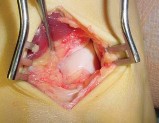

A 13-year-old obese male presents with acute-on-chronic hip and knee pain and an inability to bear weight on the affected limb. Radiographs confirm an unstable slipped capital femoral epiphysis (SCFE). He is taken to the operating room for urgent in-situ pinning. What is the most significant complication associated with attempting a forceful, intentional closed reduction of this deformity prior to hardware placement?

An unstable SCFE (defined as the inability to bear weight even with crutches) already carries a high risk of osteonecrosis. Attempting a forceful closed reduction further disrupts the fragile retinacular vascular supply to the femoral epiphysis, significantly increasing the risk of iatrogenic avascular necrosis. Gentle reduction by positioning may occur naturally, but intentional forceful reduction is contraindicated.